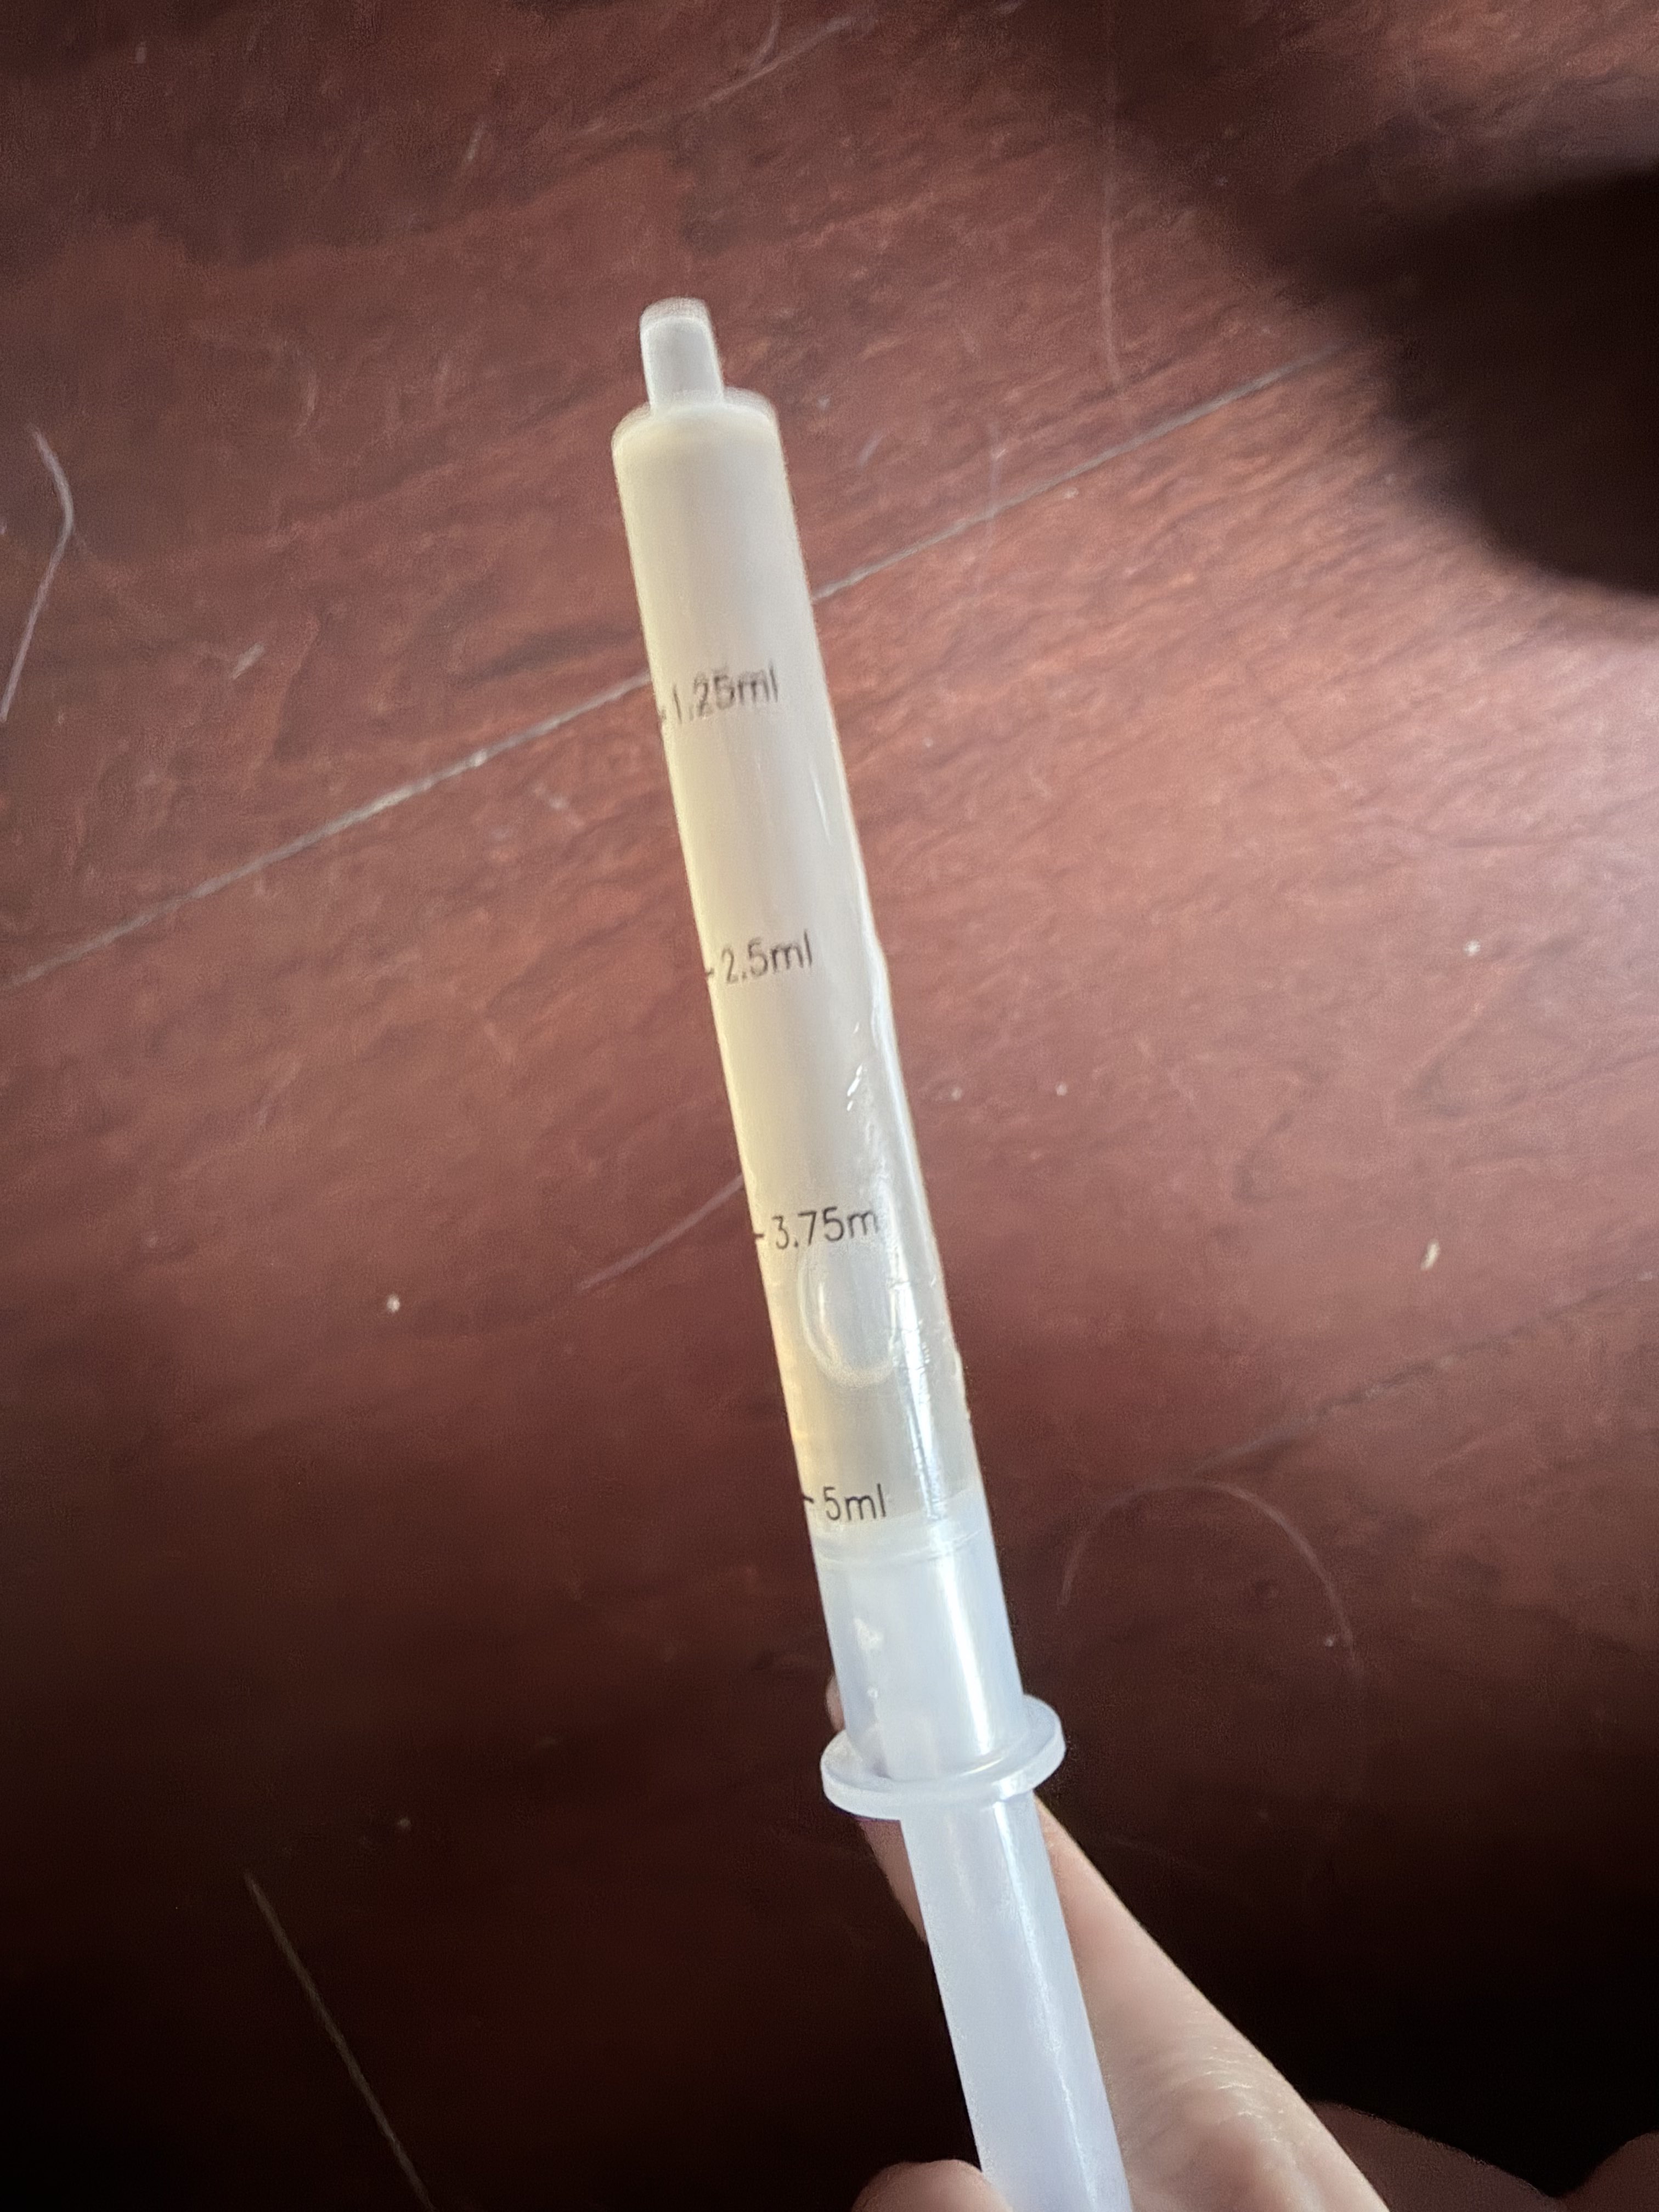

2026-03-04 19:15:41 UTC

本来是1ml,但忘记关闸血液回流,我怕把针管堵了于是又推了1ml

配合另一种麻醉就可以无痛重开了(bushi) https://t.co/Uj139Q2tBk

炽烈已极 @AnIncandescence5ml好像也没那么强……撑着清理完之后已经不困了(。)